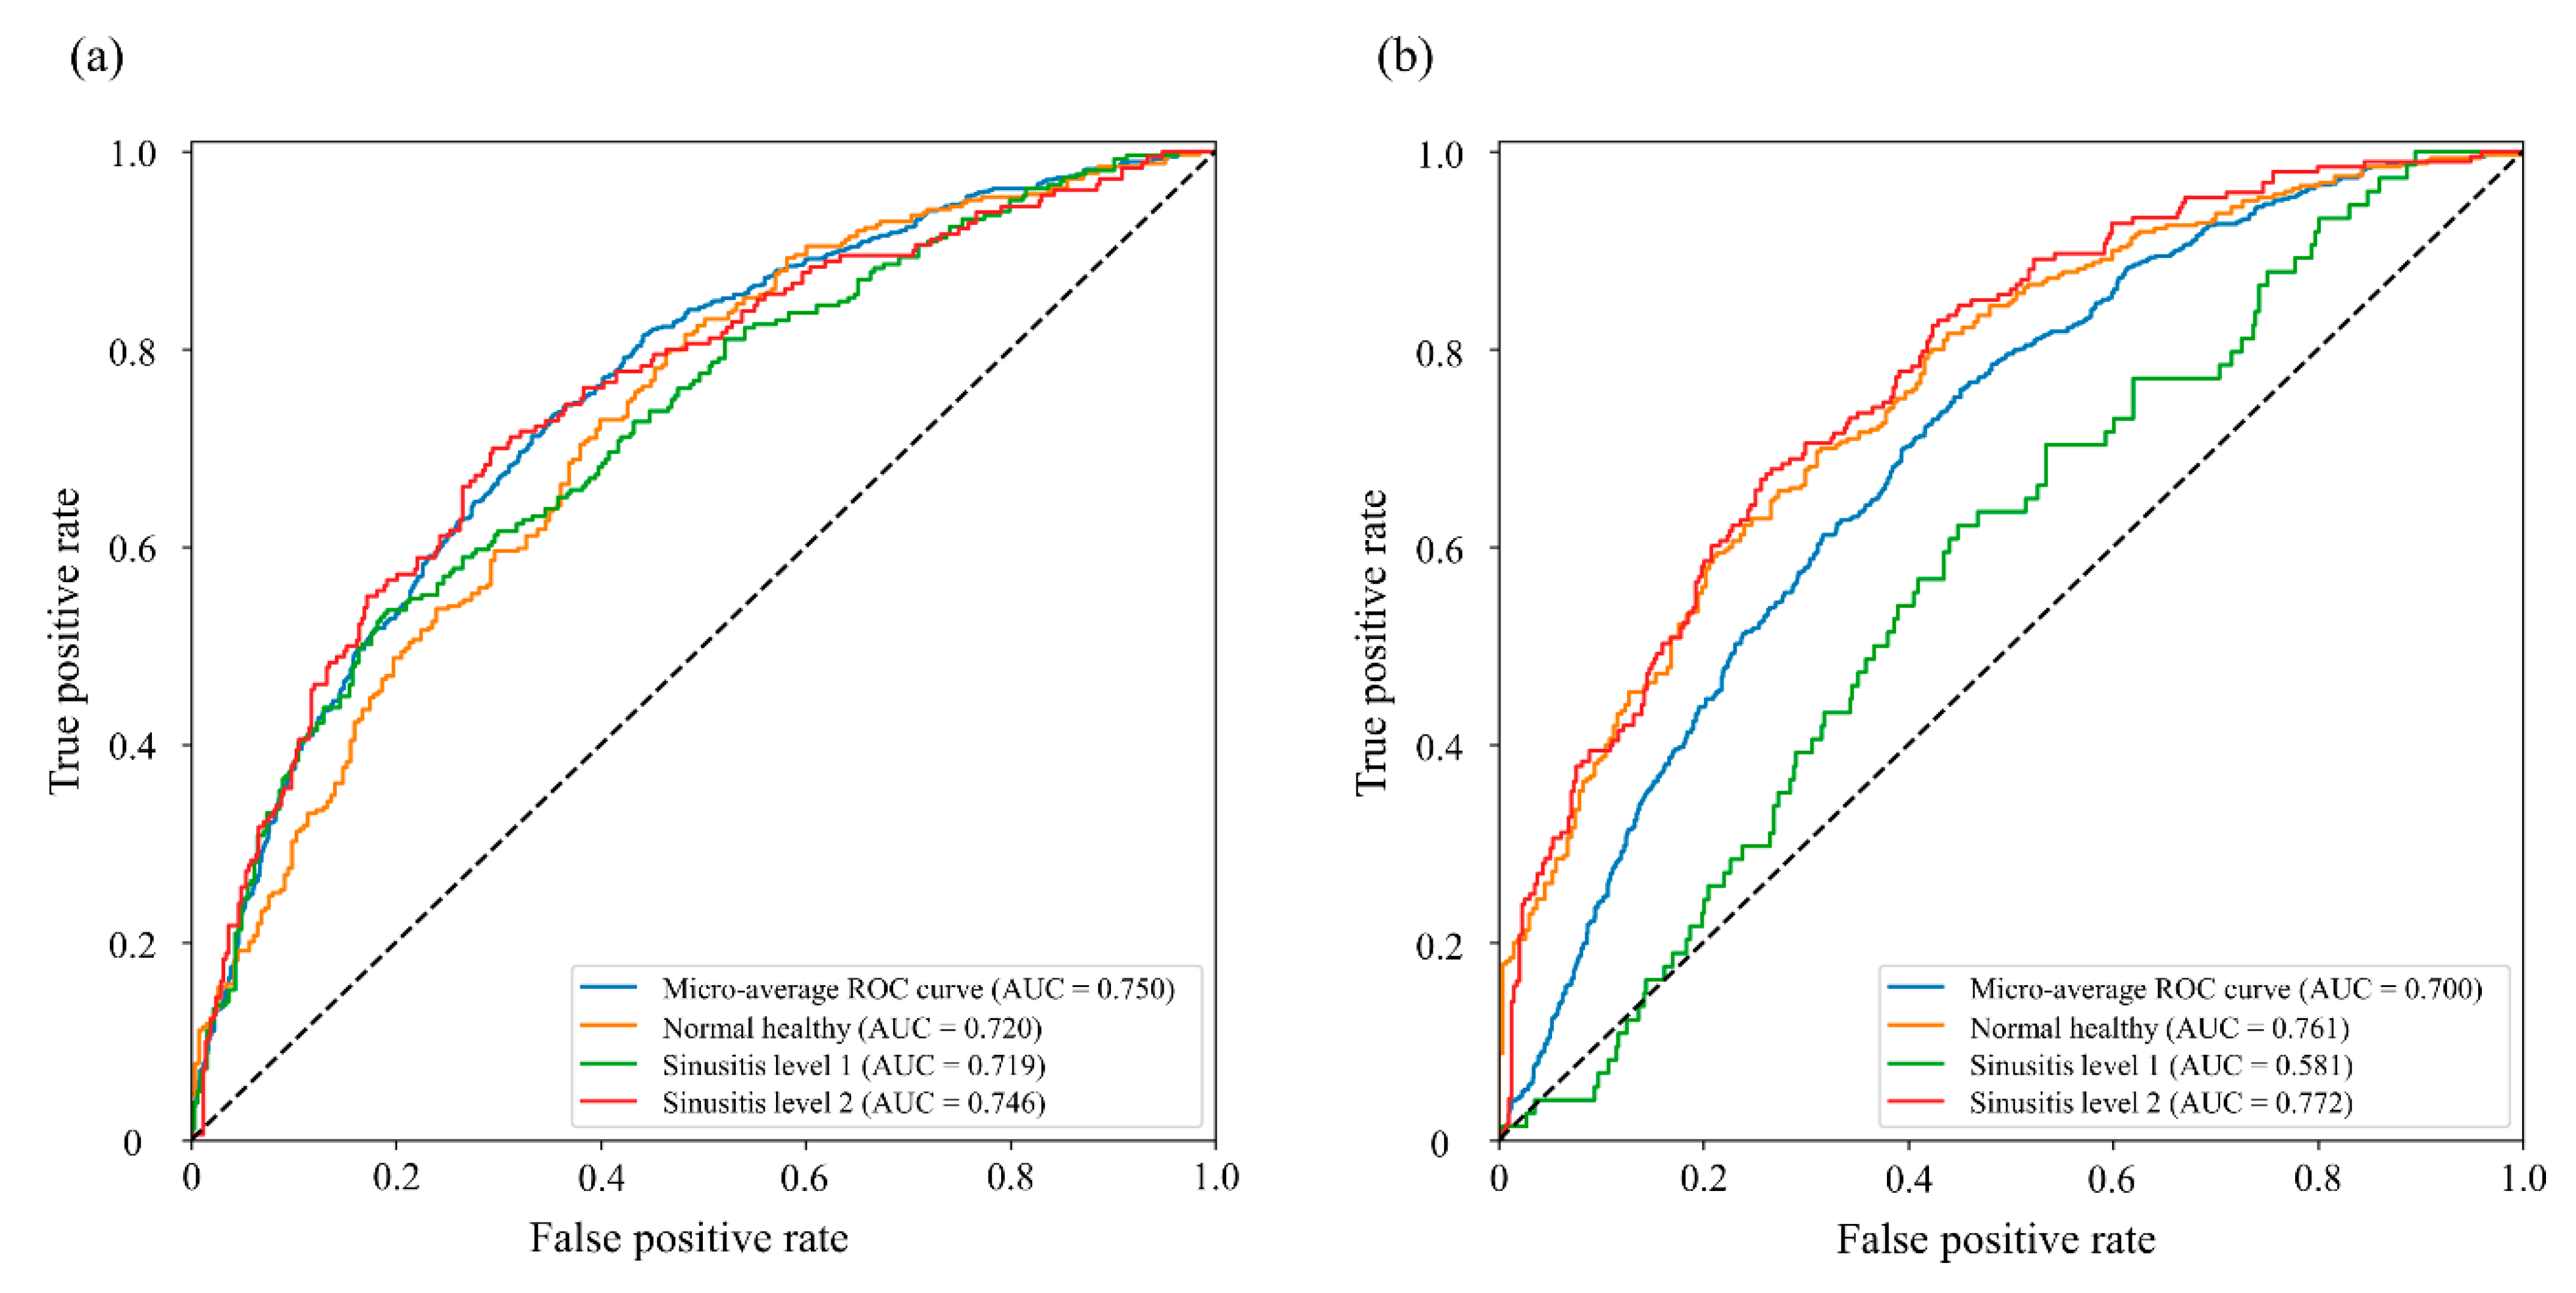

3.2. Sinusitis Classification